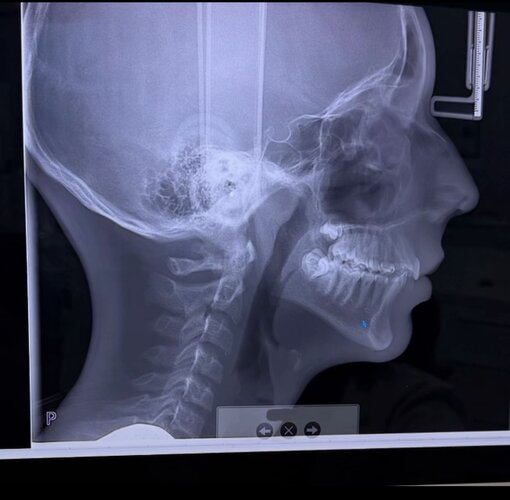

Are any people with decent knowledge in here able to help me determine what’s going on in this x-ray

Looks like you are pushing your front tooth foward probaly when you swallow cuase your bite is aligned

Bimax and counterclockwise rotation